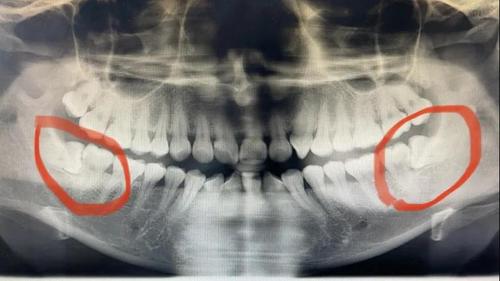

1、手术后的恢复时间

拔牙手术后的恢复时间因个体差异而有所不同,一般需要7-10天左右。在这个期间,患者需要注意休息,避免剧烈运动和咀嚼硬物,以免引发并发症。适当的饮食和口腔清洁也是恢复的关键。